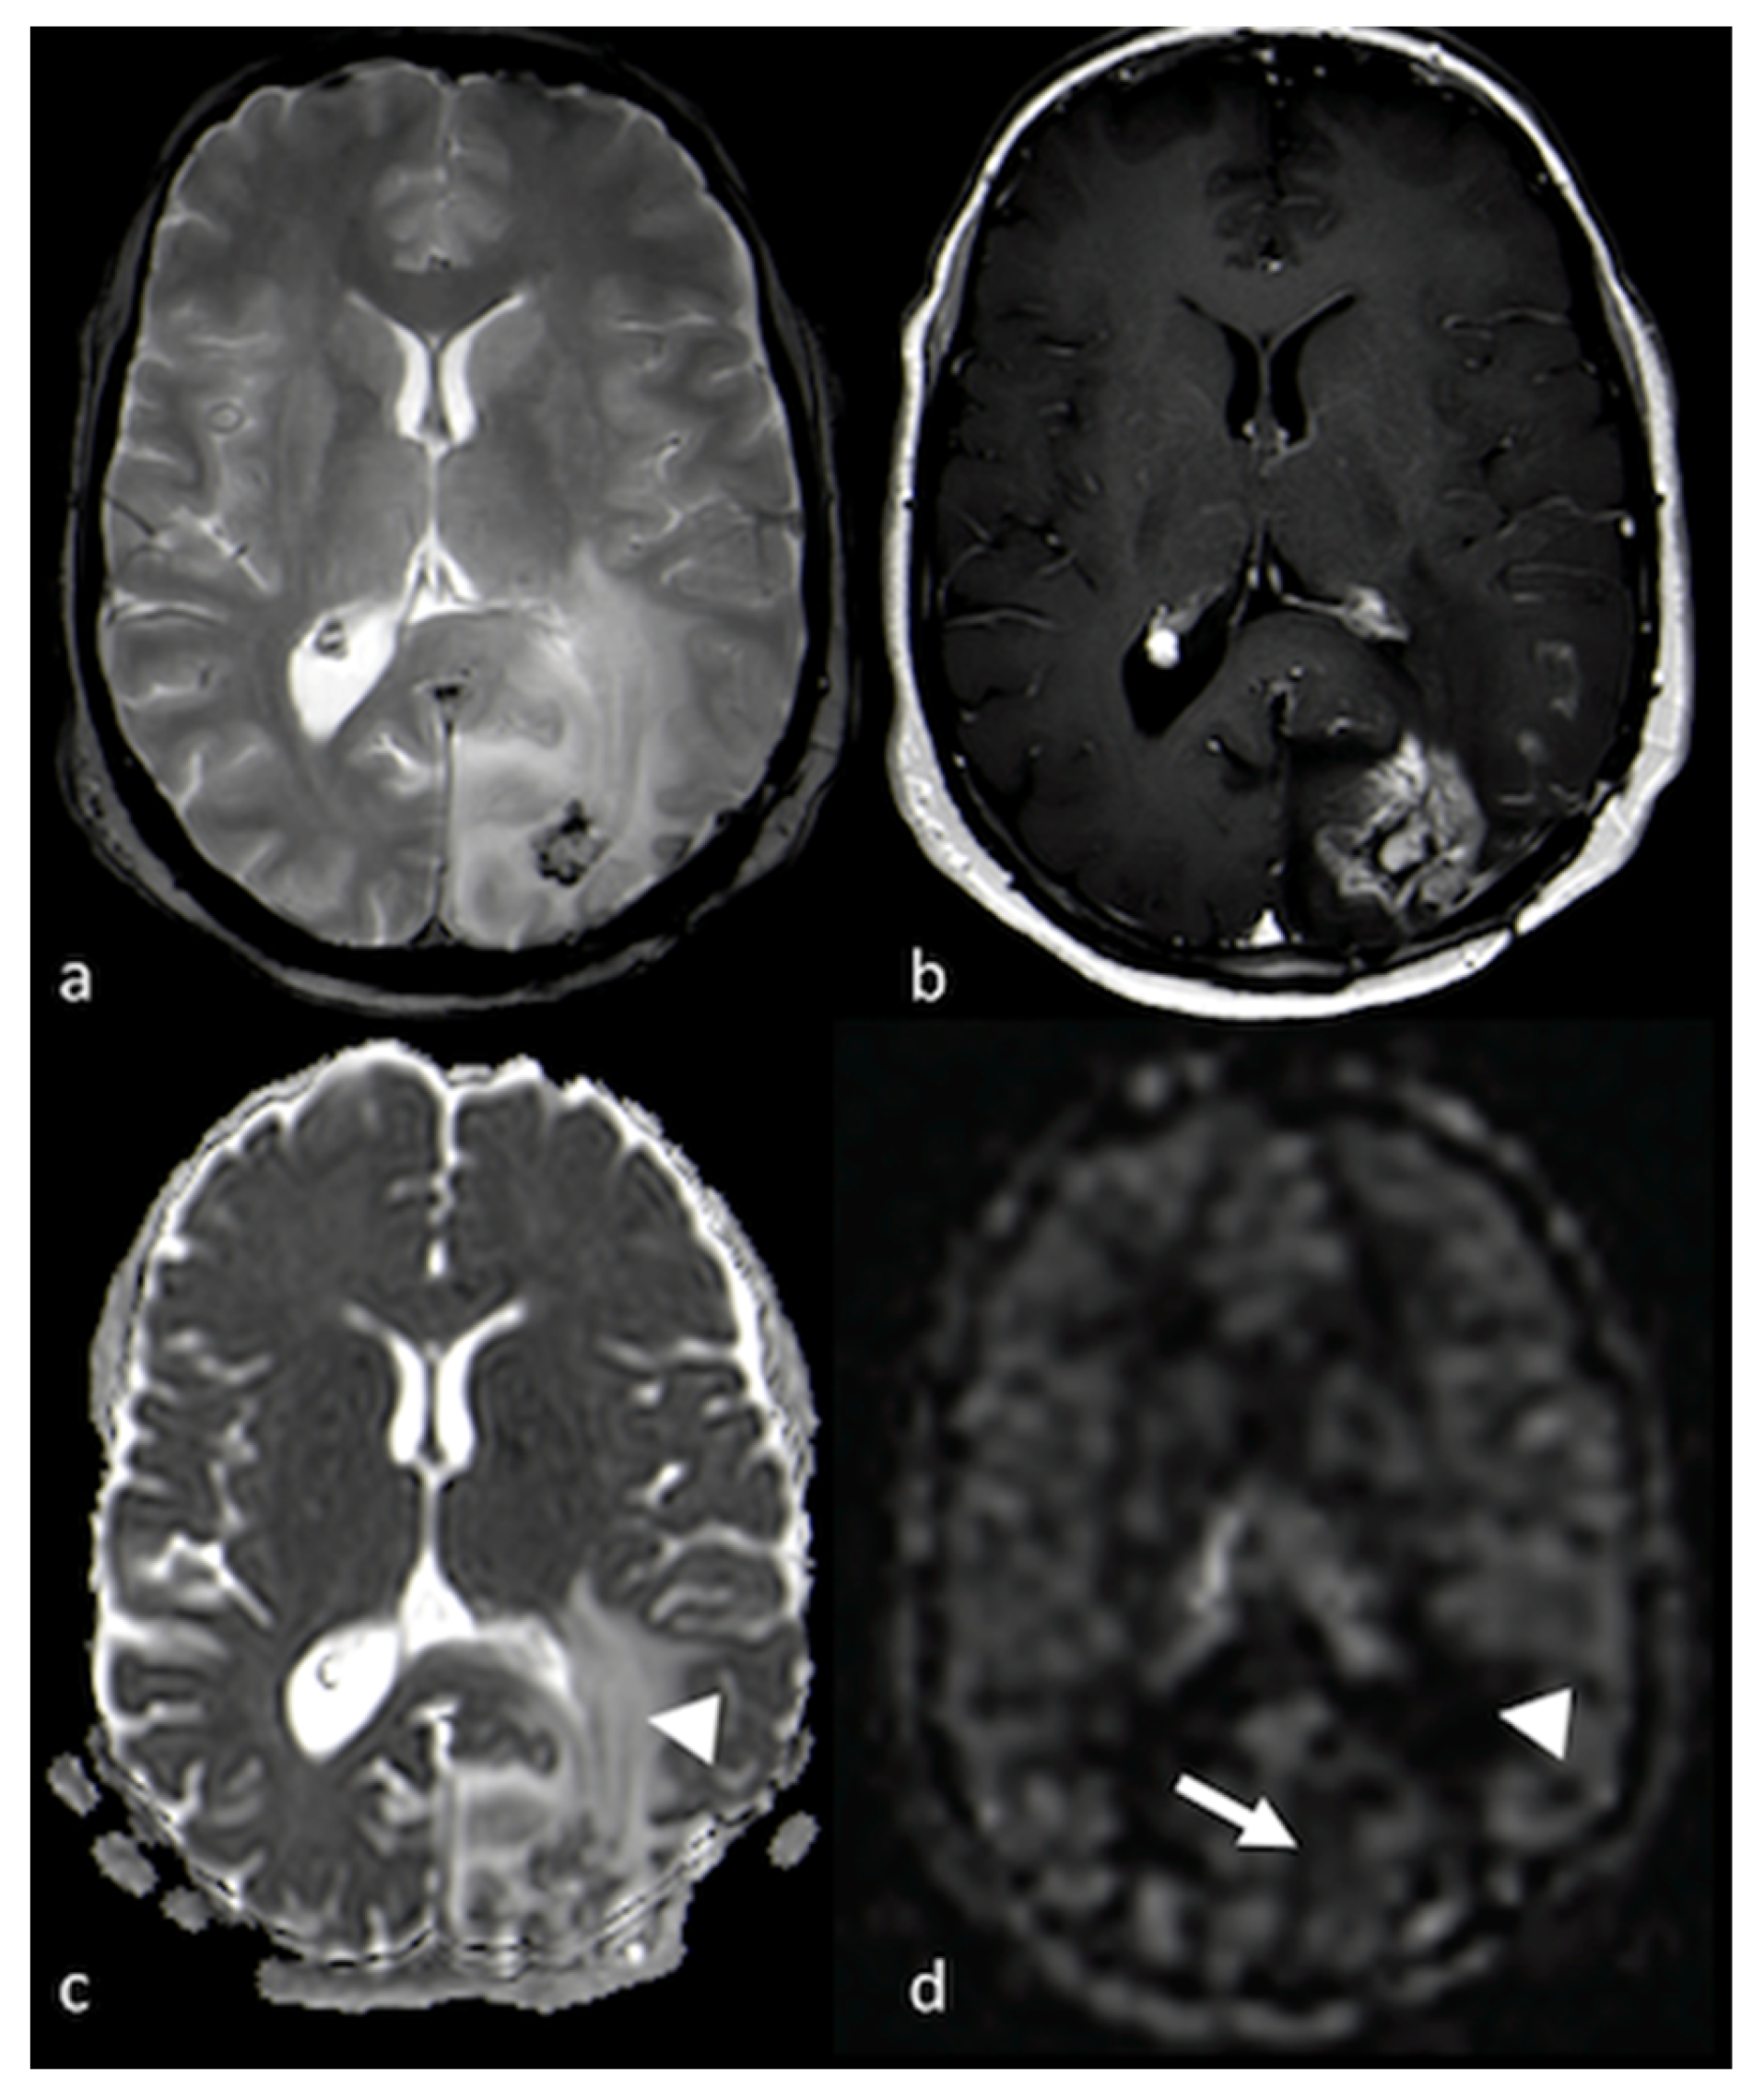

- Kickingereder, P.; Wiestler, B.; Sahm, F.; Heiland, S.; Roethke, M.; Schlemmer, H.P.; Wick, W.; Bendszus, M.; Radbruch, A. Primary central nervous system lymphoma and atypical glioblastoma: Multiparametric differentiation by using diffusion-, perfusion-, and susceptibility-weighted MR imaging. Radiology 2014, 272, 843–850. [Google Scholar] [CrossRef]

- Ma, J.H.; Kim, H.S.; Rim, N.J.; Kim, S.H.; Cho, K.G. Differentiation among glioblastoma multiforme, solitary metastatic tumor, and lymphoma using whole-tumor histogram analysis of the normalized cerebral blood volume in enhancing and perienhancing lesions. AJNR Am. J. Neuroradiol. 2010, 31, 1699–1706. [Google Scholar] [CrossRef]